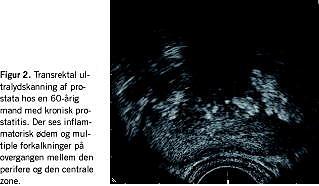

Ifølge NIH-prostatitis-klassifikationen skelnes der mellem inflammatoriske og noninflammatoriske prostatitter, men reelt set er symptomerne, de kliniske fund og behandlingstilbuddene stort set de samme [5]. Denne tilstand udgør over 90% af prostatitisgruppen og omfatter derfor en række symptomer, hvoraf flere næsten altid er til stede: dysuri, perineale smerter med udstråling retropubisk til scrotum og ud i penis, smerter ved og efter ejakulation, imperiøs vandladning med igangsætningsbesvær og nedsat strålekraft. Dertil kommer ofte forskellige psykologiske træk i form af psykiske og fysiske stress-symptomer. Ved den kliniske undersøgelse er der intet påfaldende ved rektaleksploration af prostata. TRUS (Figur 2 ) viser ofte en lille trapped prostate med forkalkninger og småcyster i både de perifere og de transitionale zoner samt inflammation ved biopsi. Eventuelt kan der påvises dilatation af ductuli deferentes og vesikler.